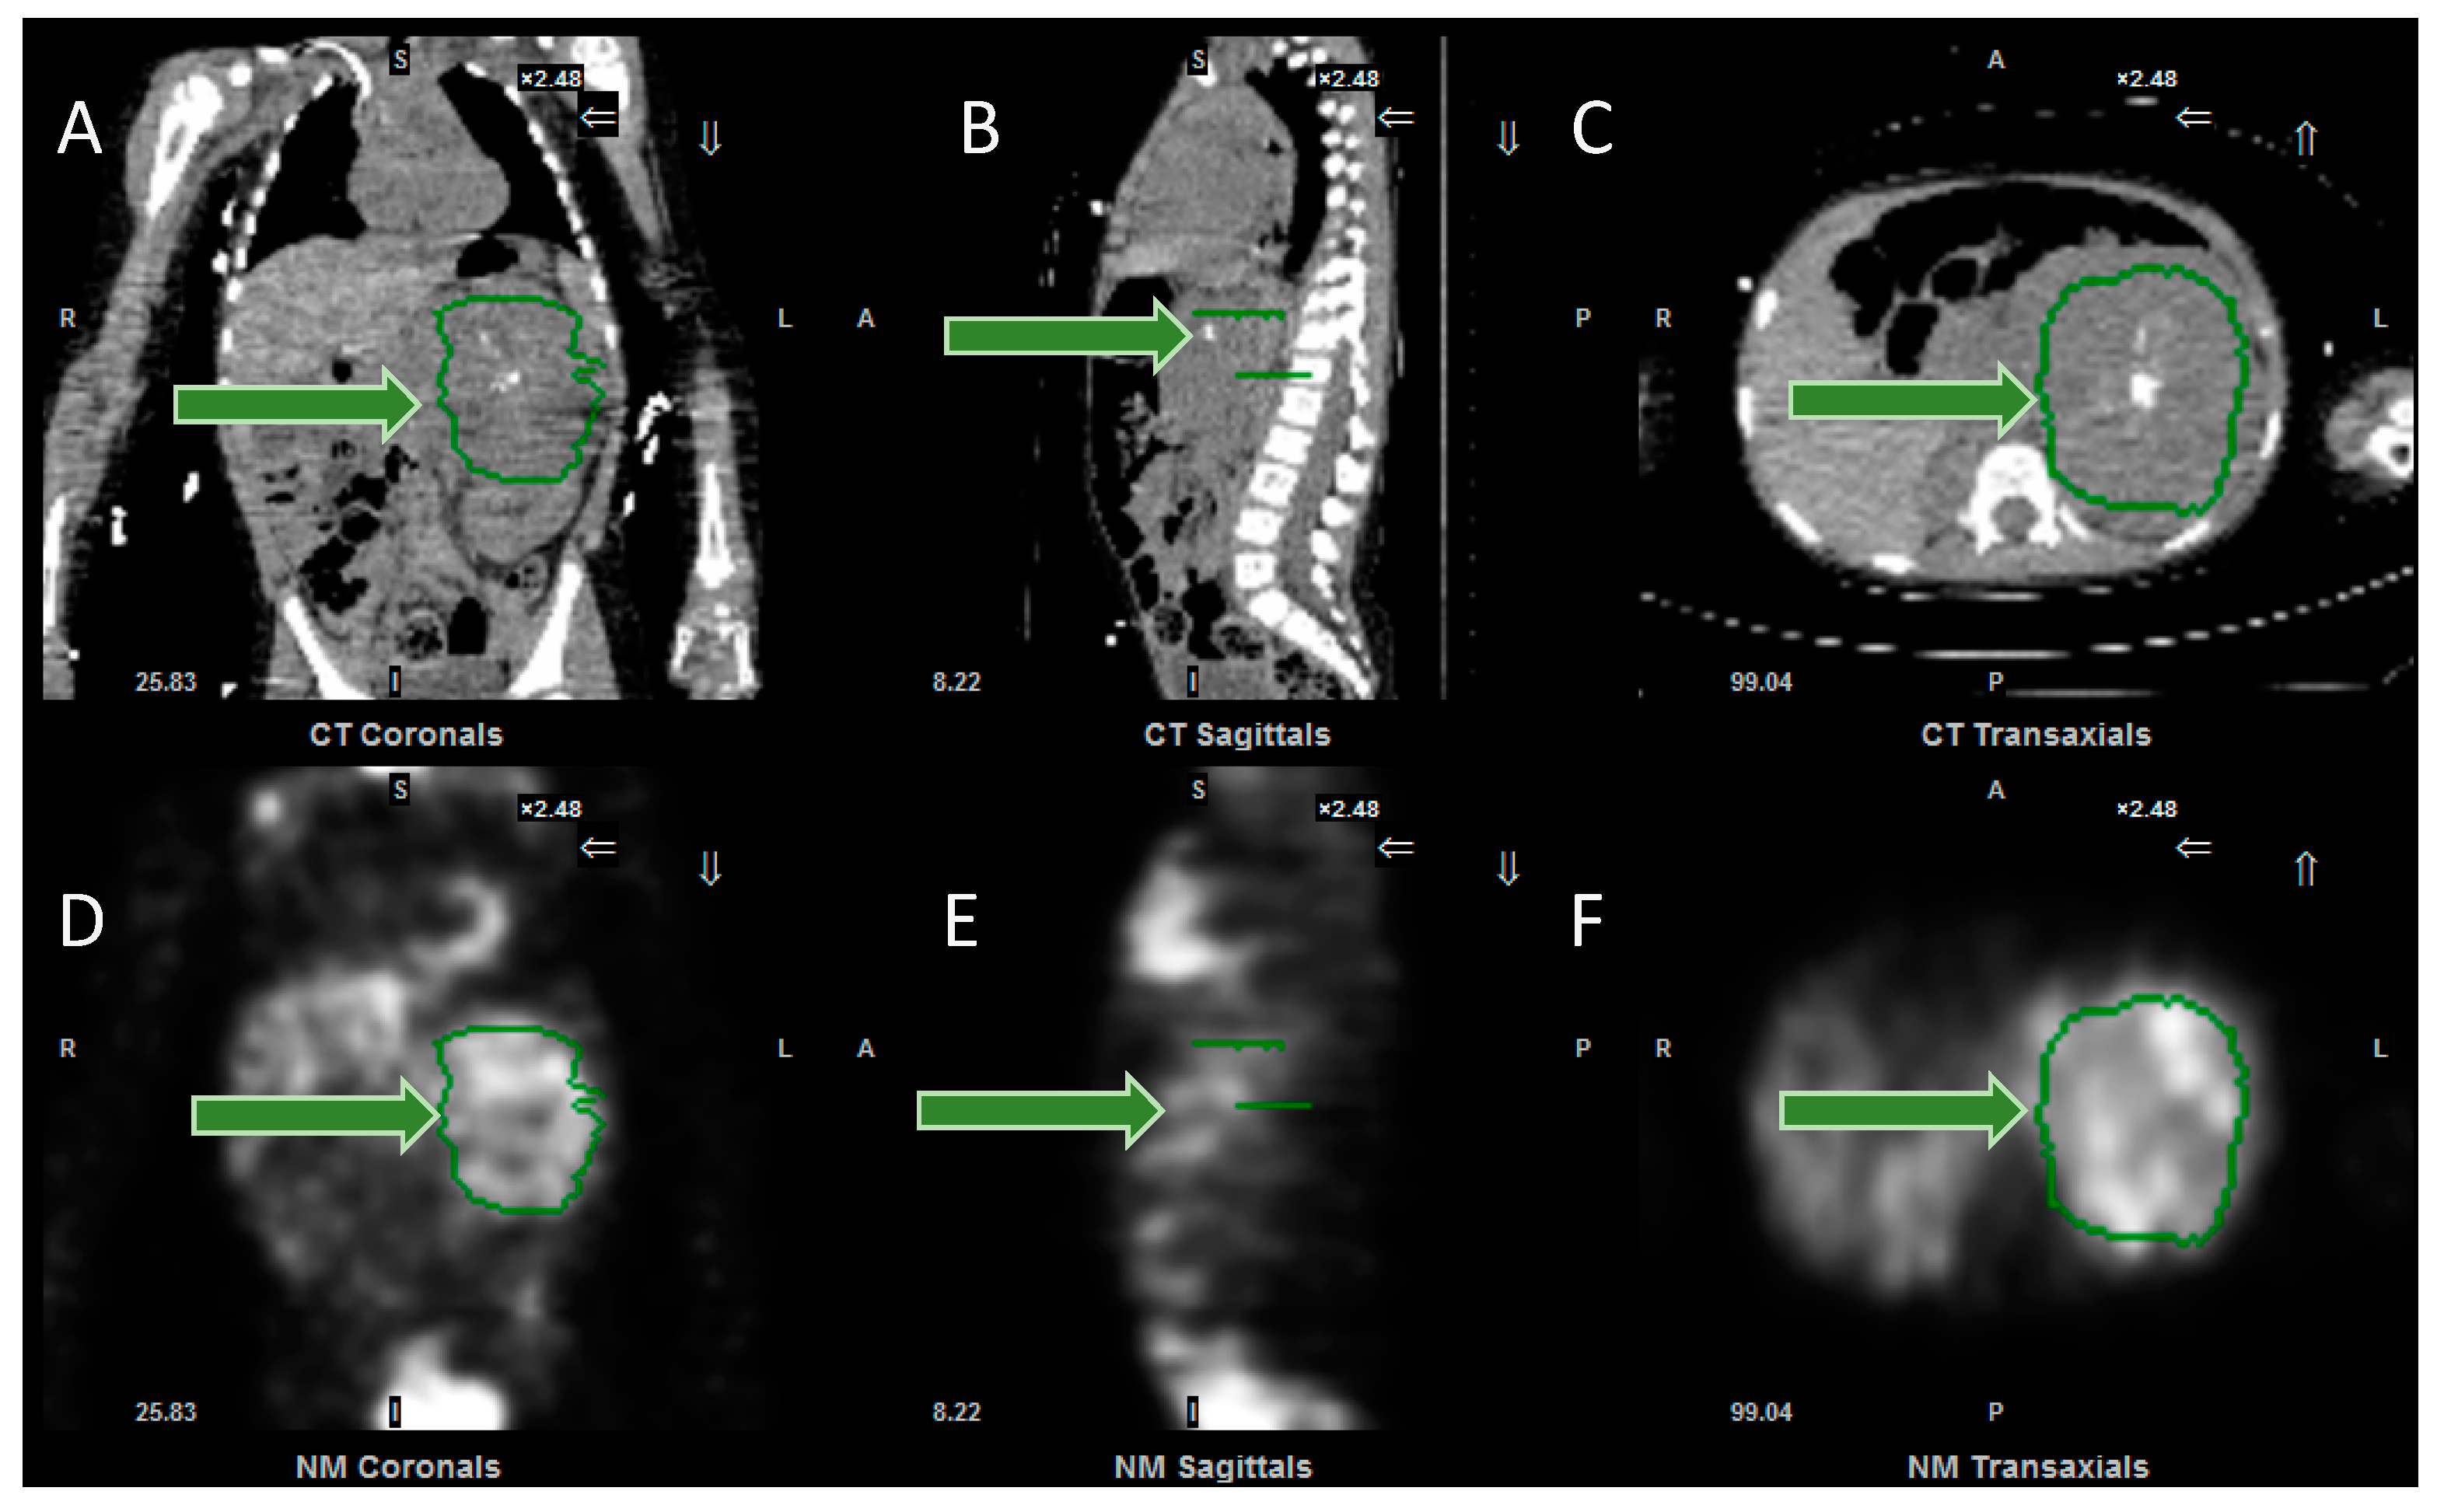

There is the prospect that in due course these semi-quantitative scores will be complemented or possibly even replaced by truly quantitative imaging. Quantitative PET CT imaging has been available for some time, with the measurement of various parameters, including standardised uptake values, metabolic active tumor volumes and total lesion glycolysis [54]. Now, software has been developed which makes it possible for SUV (standardised uptake values) to be objectively measured on SPECT CT scans (Figure 5), removing the need for more subjective image interpretation. Further research is required to determine the clinical value of serial measurements of this sort, and whether they enable greater personalisation of treatment.

Figure 5.

Images from the software to measure SPECT SUV (standardised uptake values). (A) Coronal, (B) sagittal and (C) axial CT images, together with (D) coronal, (E) sagittal and (F) axial SPECT images, demonstrating the tumour, outlined in green (arrowed). Following input of data, including administered activity and organ delineation, the system will calculate the minimum, maximum and mean (standard deviation) of the SUV, expressed as g/mL. Same patient as in Figure 1.